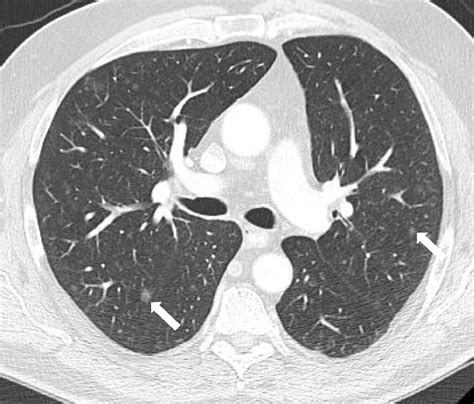

Pulmonary and Cardiac Manifestations

In addition to the brain and kidneys, Tuberous Sclerosis Radiology must account for pulmonary and cardiac health. Lymphangioleiomyomatosis (LAM), a disease characterized by the proliferation of atypical smooth muscle cells in the lungs, primarily affects adult women with TSC. High-resolution computed tomography (HRCT) is the definitive modality for identifying the characteristic diffuse thin-walled cystic changes in the pulmonary parenchyma.